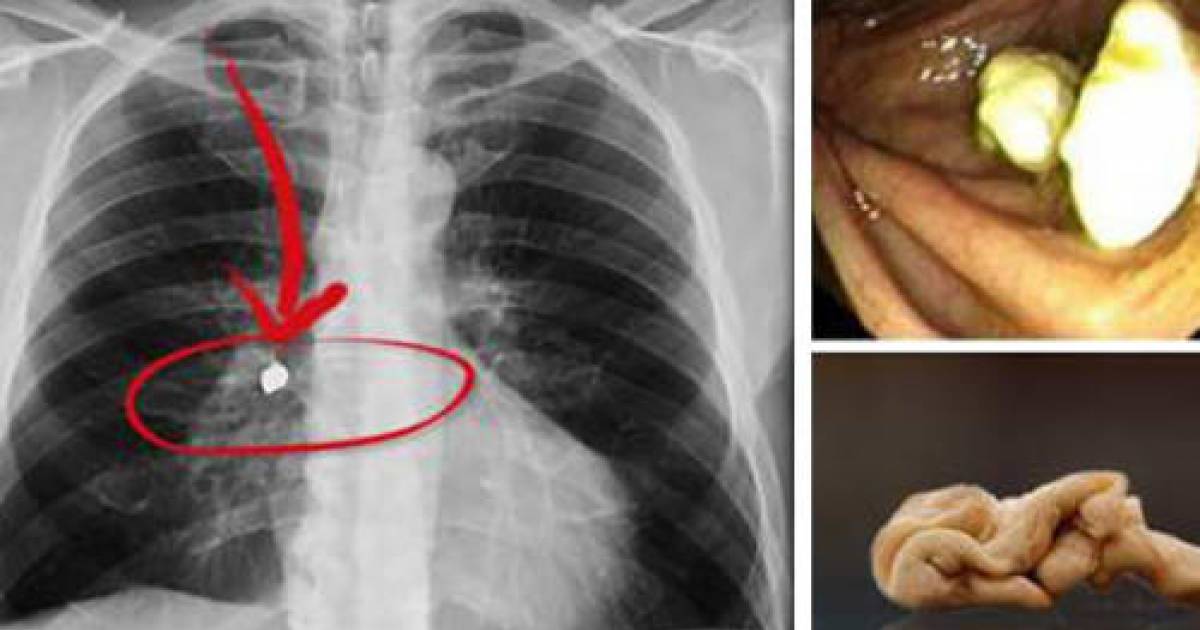

Side Effects Swallowing Chewing Gum . what are some side effects of chewing gum? although chewing gum is designed to be chewed and not swallowed, it generally isn't harmful if swallowed. Will swallowing gum make you sick? learn about what happens if you've swallowed chewing gum. As a child, your elders might have warned you that swallowing gum is bad for you. apart from the risk of obstruction, the act of chewing gum leads to swallowing more saliva and more air,. for most people, swallowing gum shouldn’t have any side effects unless you have swallowed a lot of it. when you swallow a small amount of gum, it will pass out of your body in your bowel movements within a few.